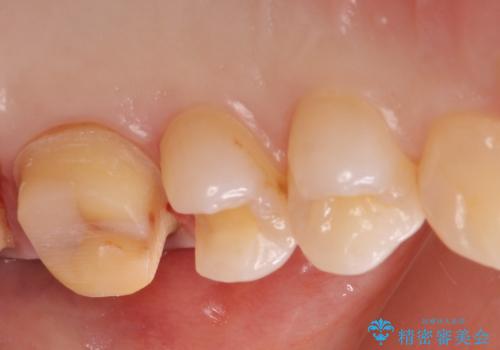

- 銀が目立つので白くしたいとの事で来院。

銀の詰め物を拡大鏡下で取り除き、う蝕がないことを確認してから

ZrCrの被せ物で治療を行いました。

銀の詰め物の範囲が大きいほど

やりかえをする時、セラミックの詰め物だと割れるリスクがあるため

ZrCrの被せ物のご案内をする事があります。